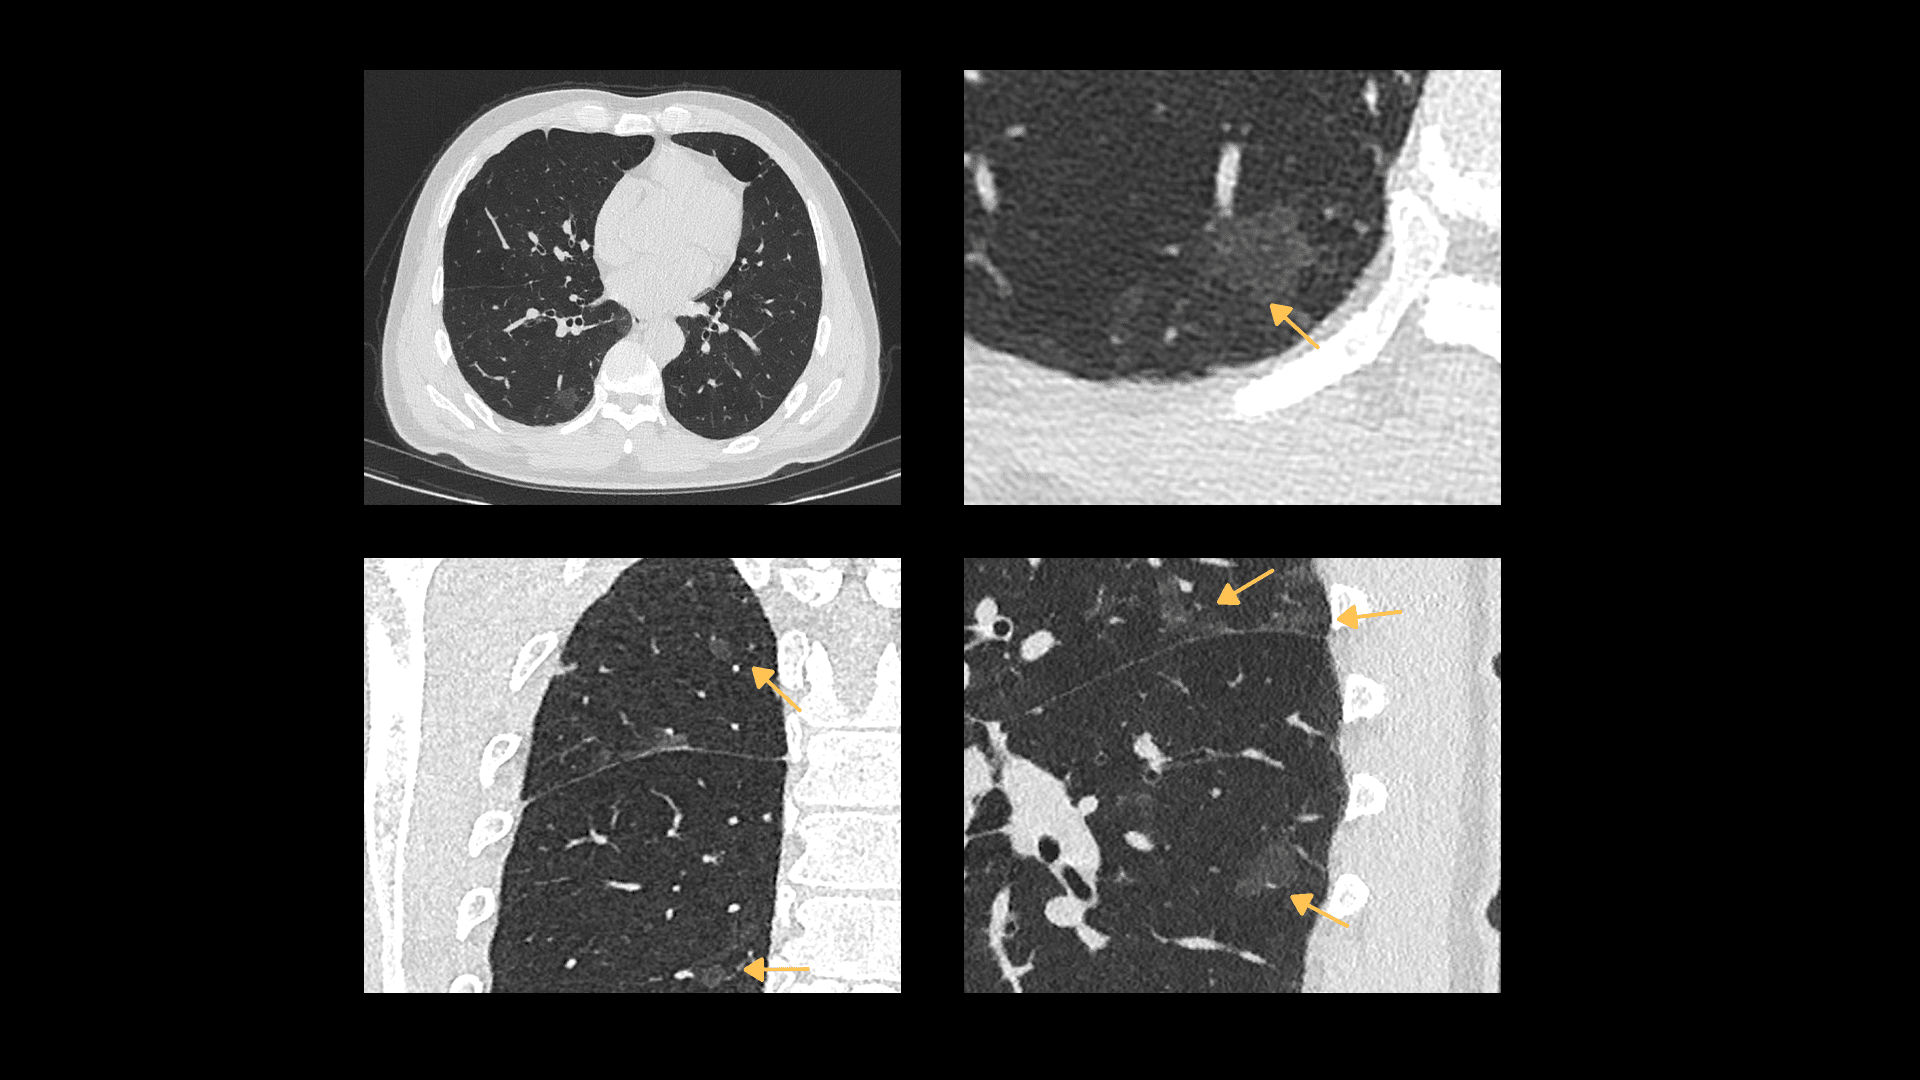

Imagistică Toracică cu Grosime de Secțiune de 0.55 mm

Detectorul Z al sistemului uCT Orion Extra oferă o grosime minimă a secțiunii de 0.55 mm, permițând o delimitare mai precisă și o vizualizare îmbunătățită a opacităților de tip ground-glass (GGO), cu definirea clară a marginilor leziunilor pulmonare.

| Parametri scanare |

Timp rotație: 0.71 s / rotație kV: 120 mAs: 30 CTDIvol: 2.9 mGy Doză efectivă: 1.5 mSv |

| Parametri reconstrucție |

Matrice: 512 × 512 Grosime secțiune: 0.55 × 0.55 mm HIR: B_SHARP_C WW/WL: 1500 / -500 |